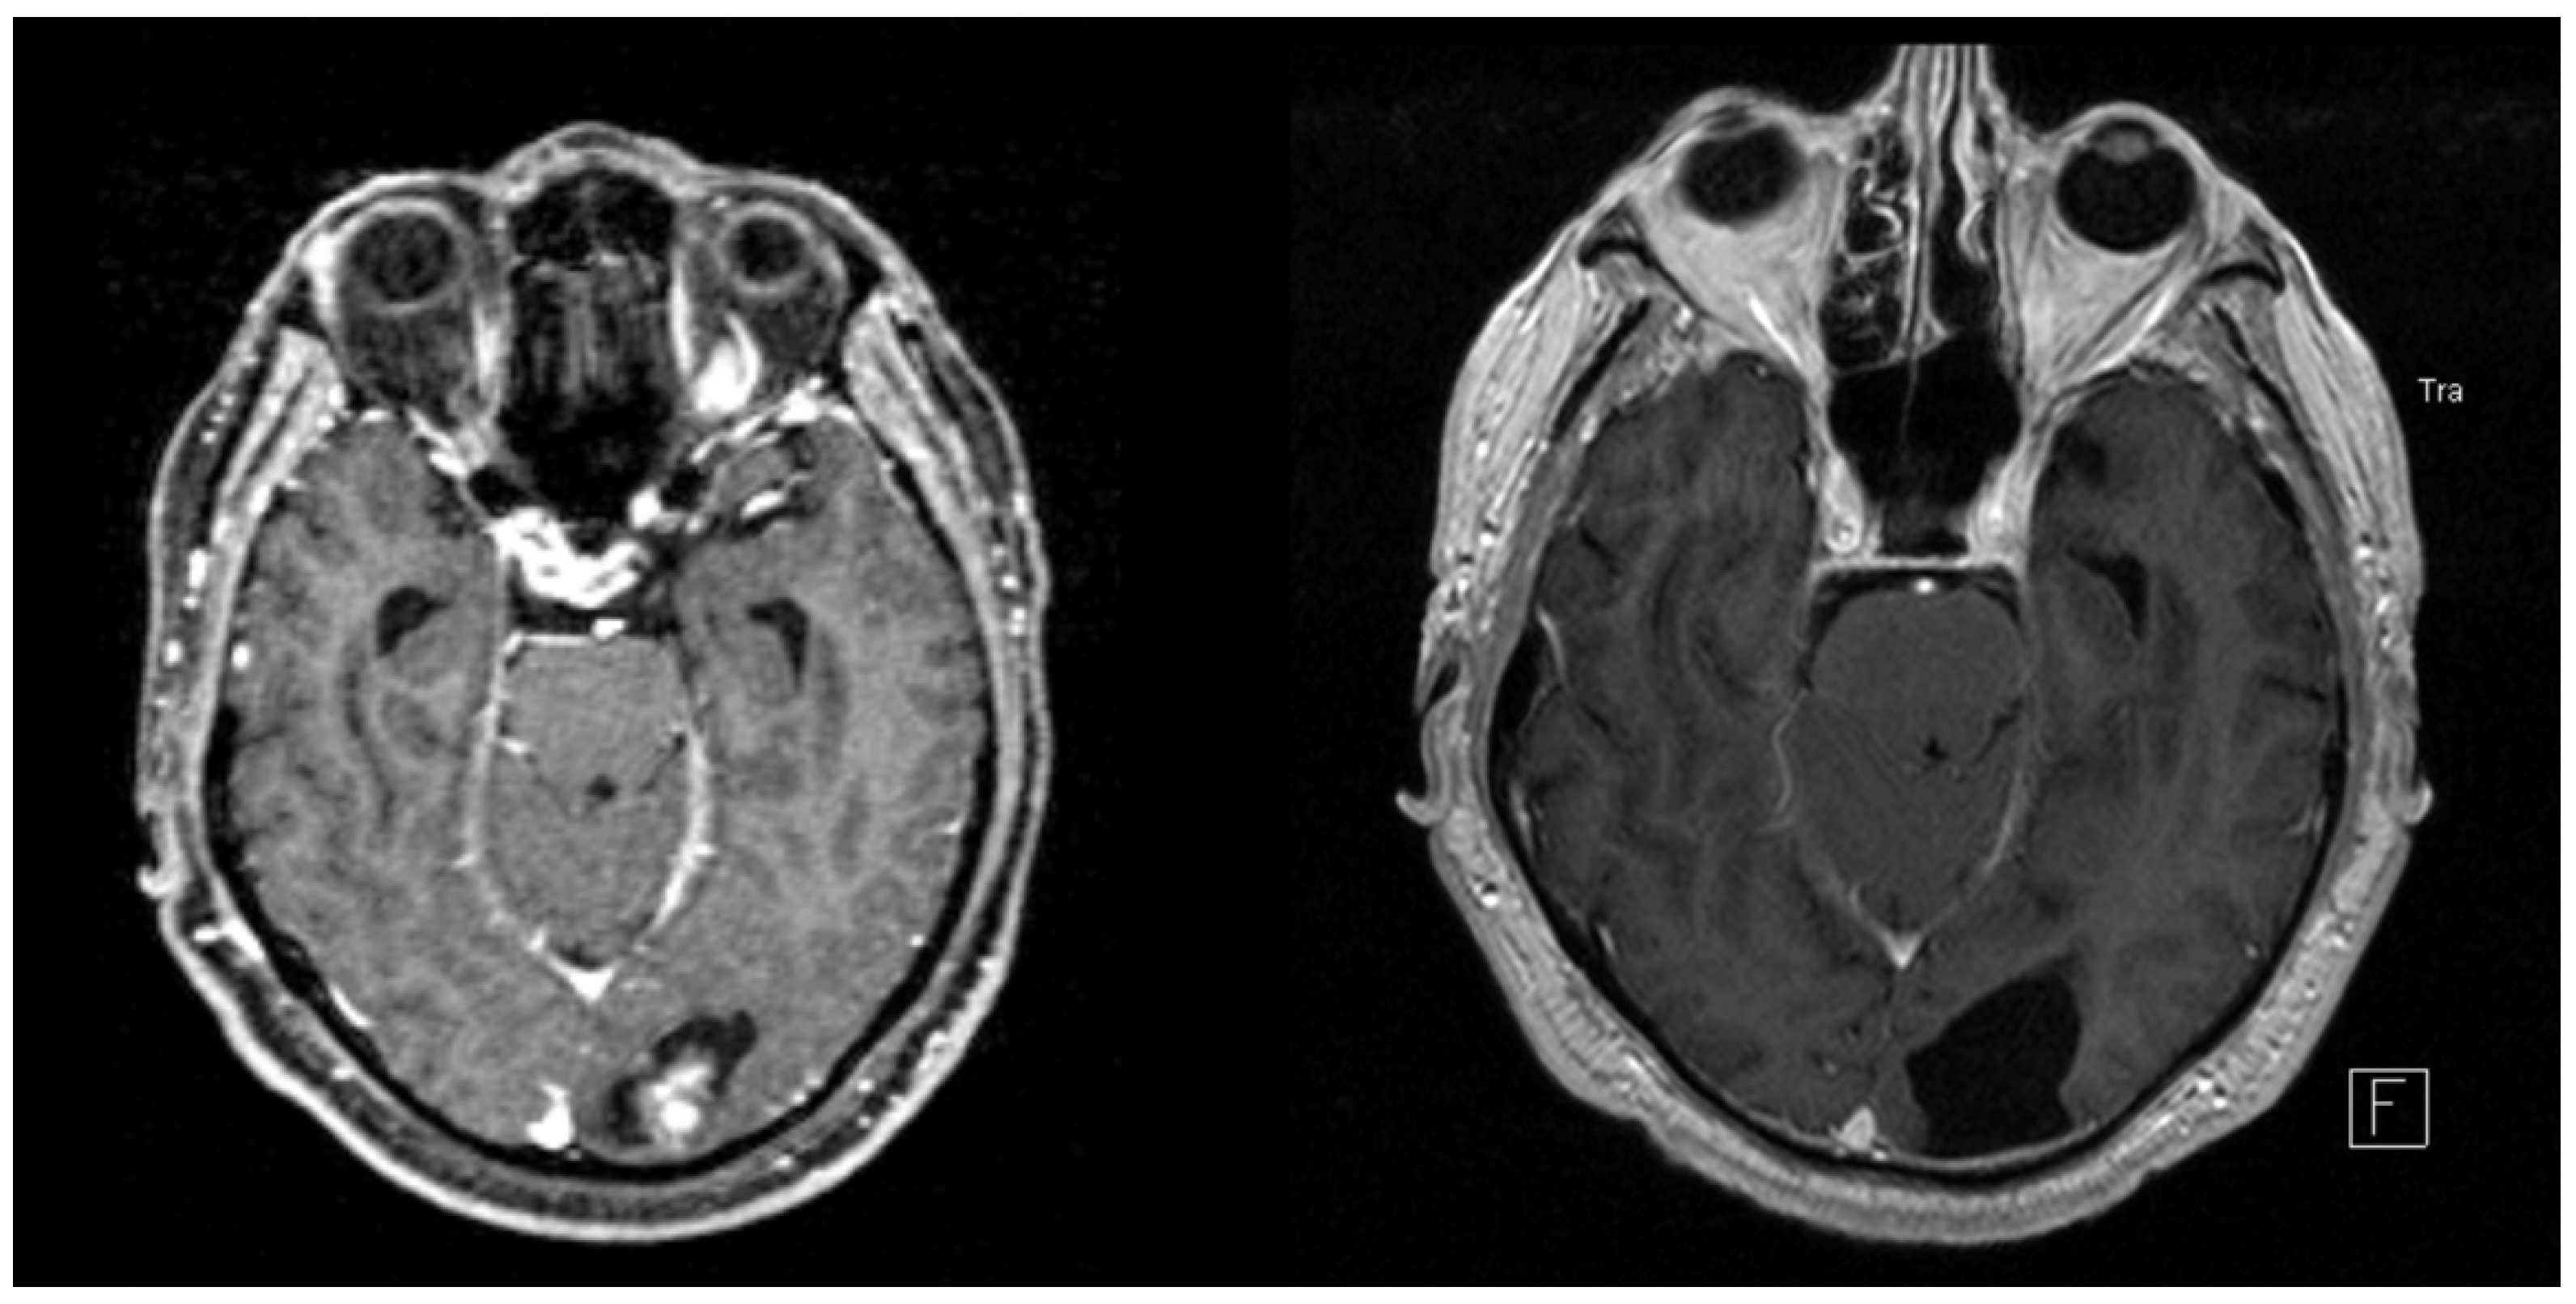

| BM with ICH during follow-up, n (%) | 9 (9) |